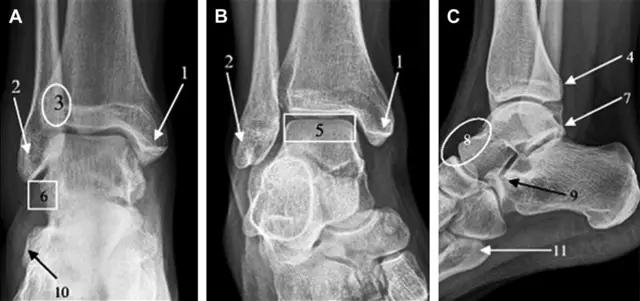

首先,来看踝关节骨折的高危区(图 1)。

图 1 踝部探查模板。阅片时,需对踝关节的前后位片(A)、内旋转位片(B)侧位片(C)仔细阅读,逐一详细排查。上图中的骨折:1. 内踝骨折,2. 外踝骨折,3. 胫骨结节骨折,4. 胫骨后踝骨折,5. 距骨骨软骨骨折,6. 距骨外侧突骨折,7. 距骨后突骨折,8. 距骨舟骨关节背侧骨折,9. 跟骨前突骨折,10. 跟骨骨折嵌插入趾短伸肌,11. 第五跖骨底骨折